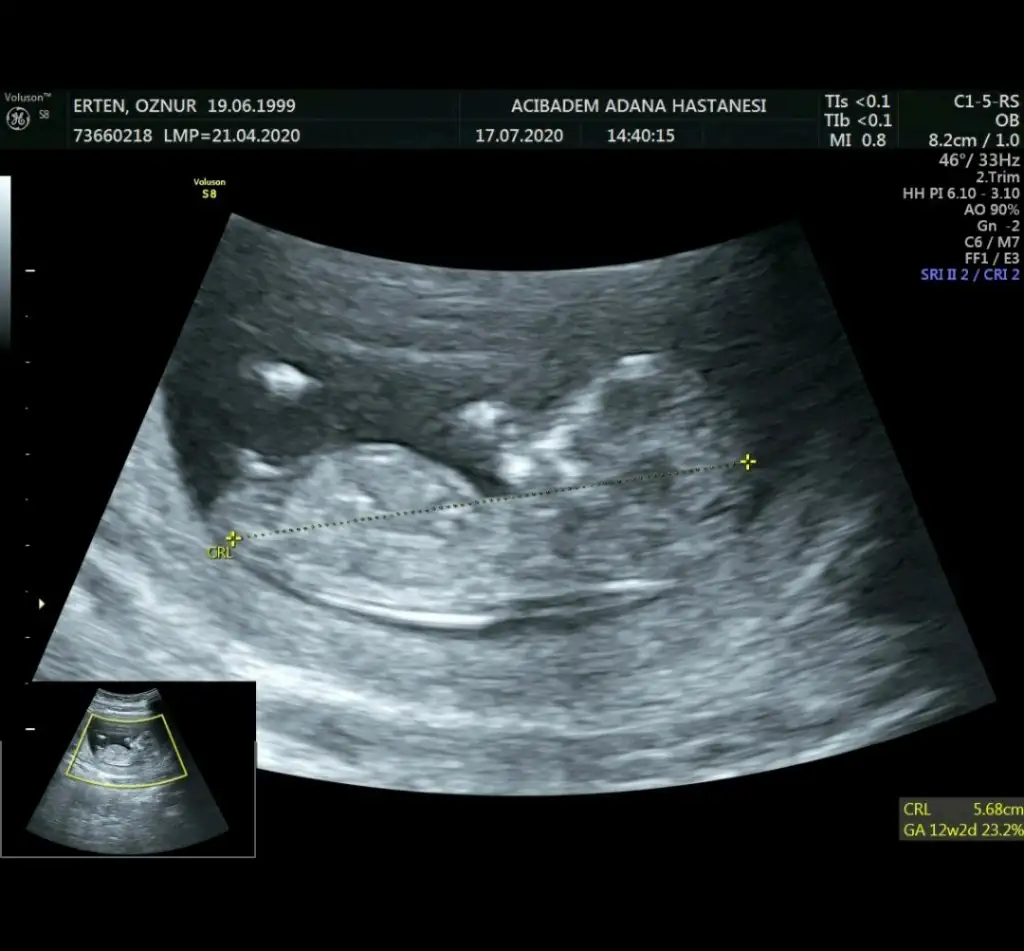

En net olanı bu malesef başka yok. Doktor erkeğe benzetti ama 1 ay sonra kesinleşir dedi. Yorumunuz için teşekkürler hayırlısı olsun :)Bebek hafif yan pozisyonda emin olmamakla birlikte sanki kız tekrar usg paylaşın

Dogrudur o zamam emin olamadım nubu ne dik nede paraleldi bebek yan pozisyonda olunca emin olamadım başka usg ile teyit etmek istemiştim hayırlısı olsun sizin içinEn net olanı bu malesef başka yok. Doktor erkeğe benzetti ama 1 ay sonra kesinleşir dedi. Yorumunuz için teşekkürler hayırlısı olsun :)

Erkek gibiBir başka ultrason istemiştiniz bunlar var elimde bacaklarini bağlamışti öylece duruyorduheyecanla yorumunuzu bekliyorumm Ikra meyra